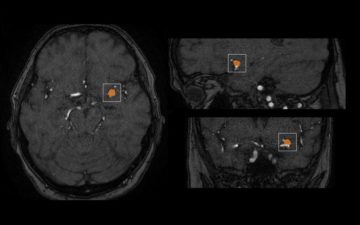

mediaire führt mit mdbrain weltweit ersten neuroradiologischen KI-Assistenten mit vollautomatischer Detektion von Aneurysmen ein

Für die Differenzialdiagnostik und Verlaufskontrolle von Erkrankungen des Gehirns ist die MagnetResonanzTomographie (MRT) eine wichtige Säule. Diese kann in Kombination mit moderner Computertechnik und Künstlicher Intelligenz (KI) zusätzliche quantitative Informationen zur Verfügung stellen, die zu besseren Ergebnissen für Patienten führen. Für die Erkennung von Aneurysmen – krankhaften Aussackungen von Hirngefäßen Weiterlesen…